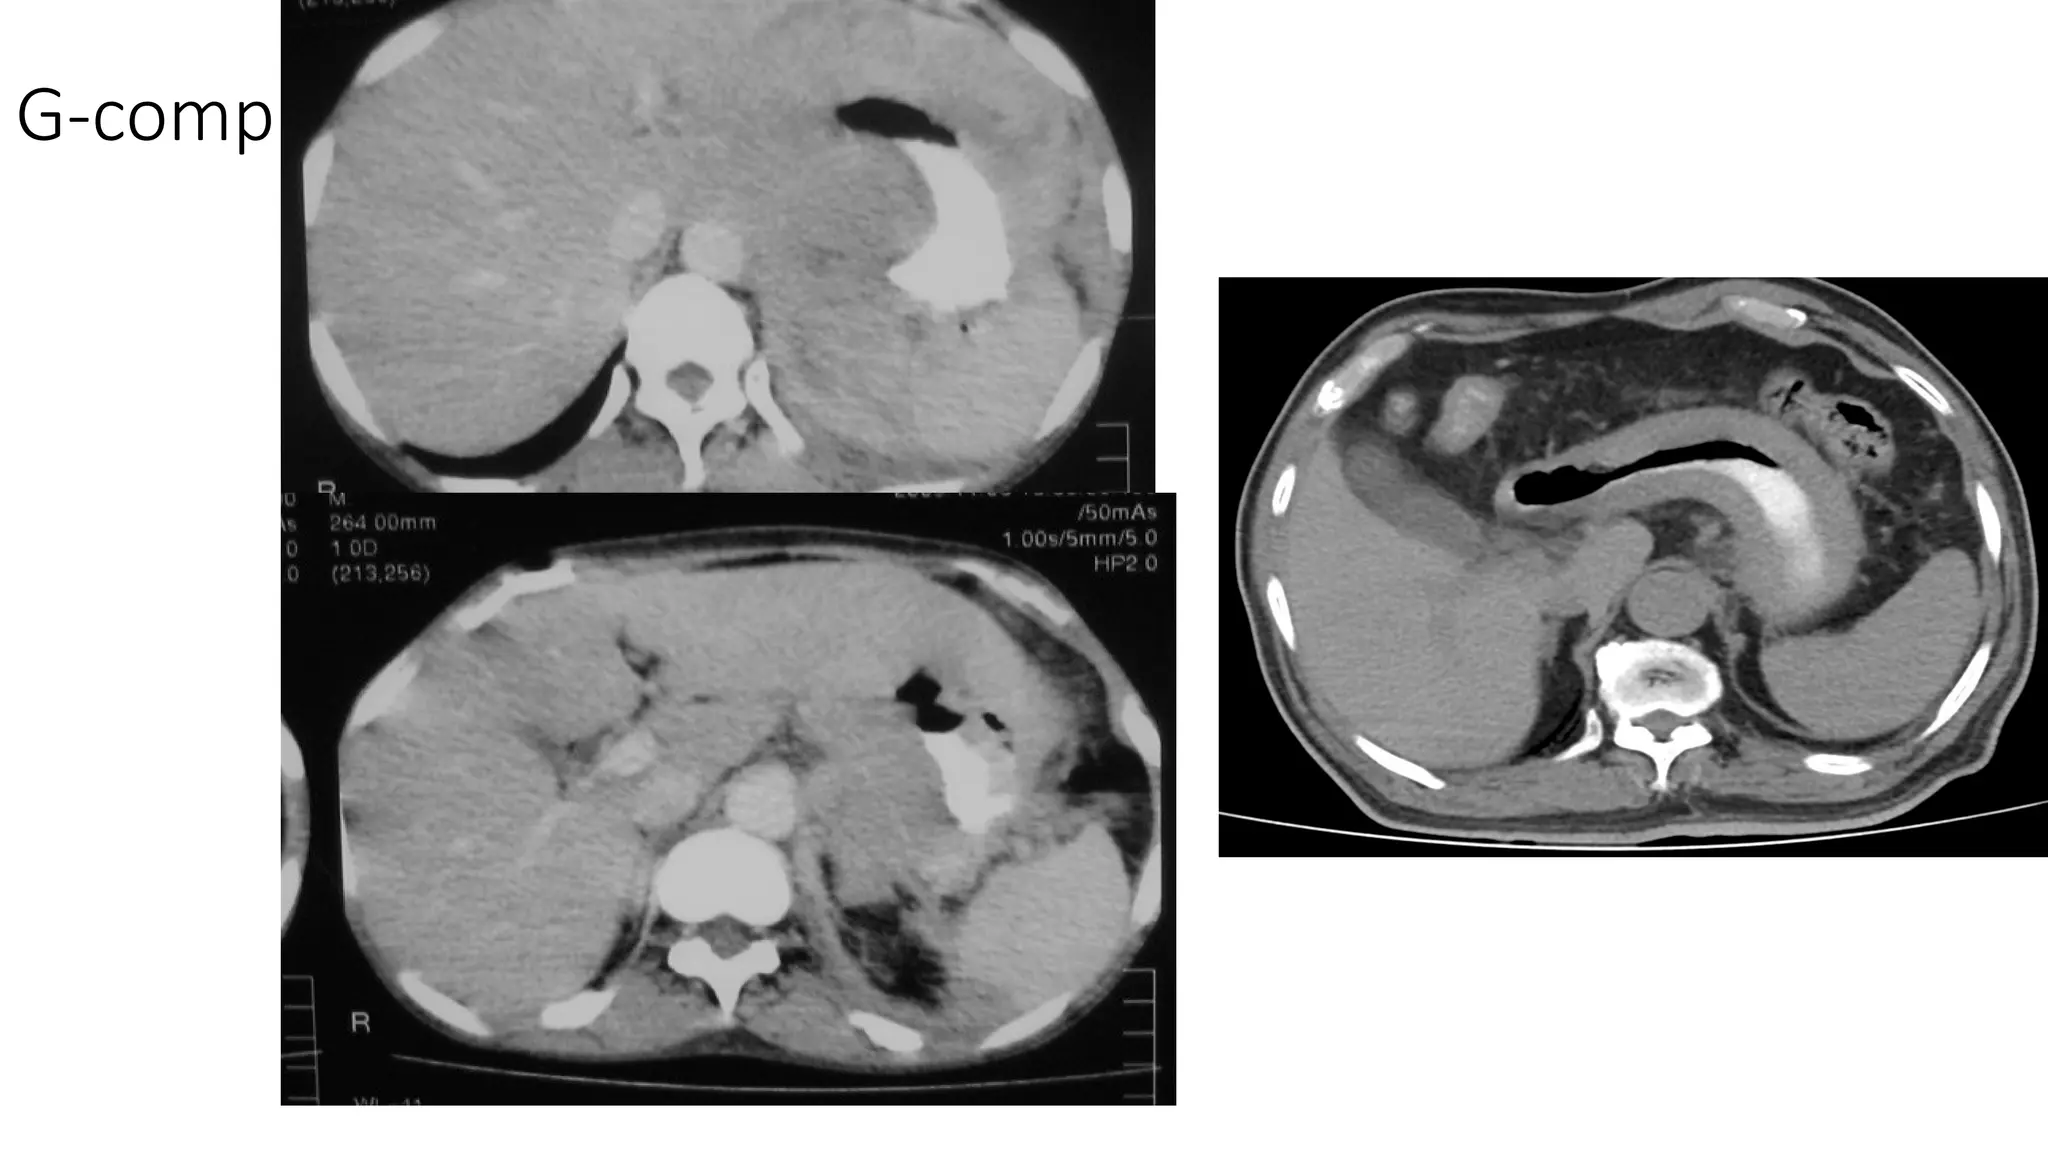

The document lists various components and classifications related to the gastro-intestinal system. It includes multiple codes and identifiers associated with different aspects of this biological system. The content appears to be a structured categorization rather than a narrative or descriptive text.